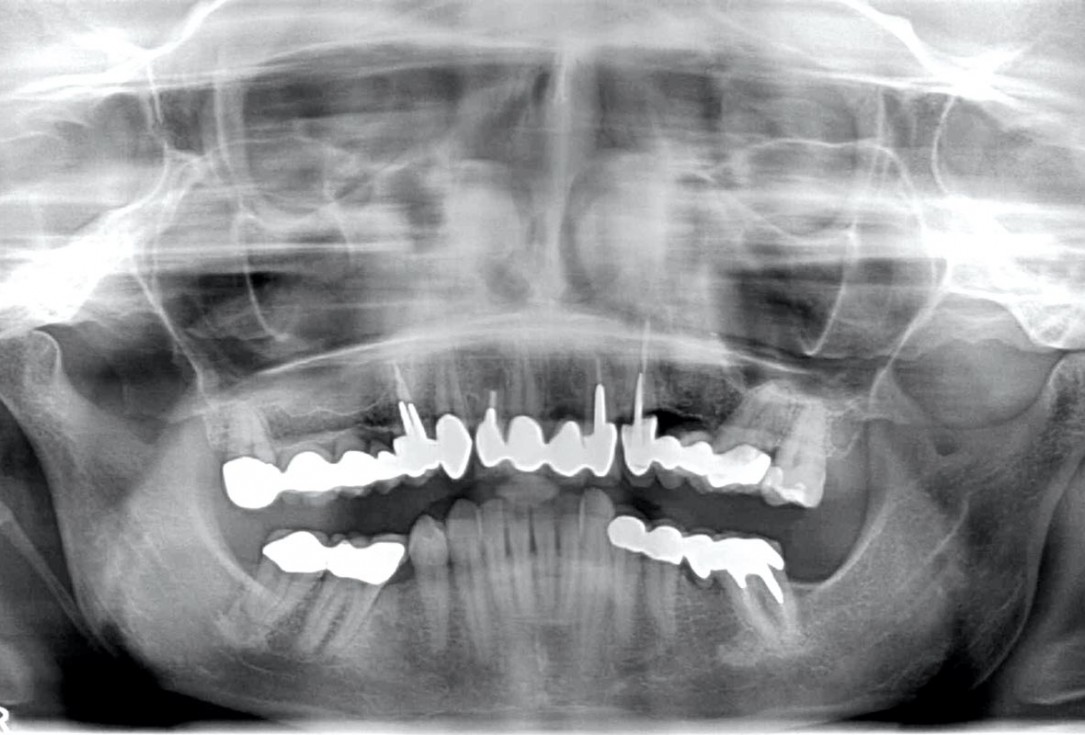

Instable bridge situation with abscess formation at tooth #15 after apicoectomy